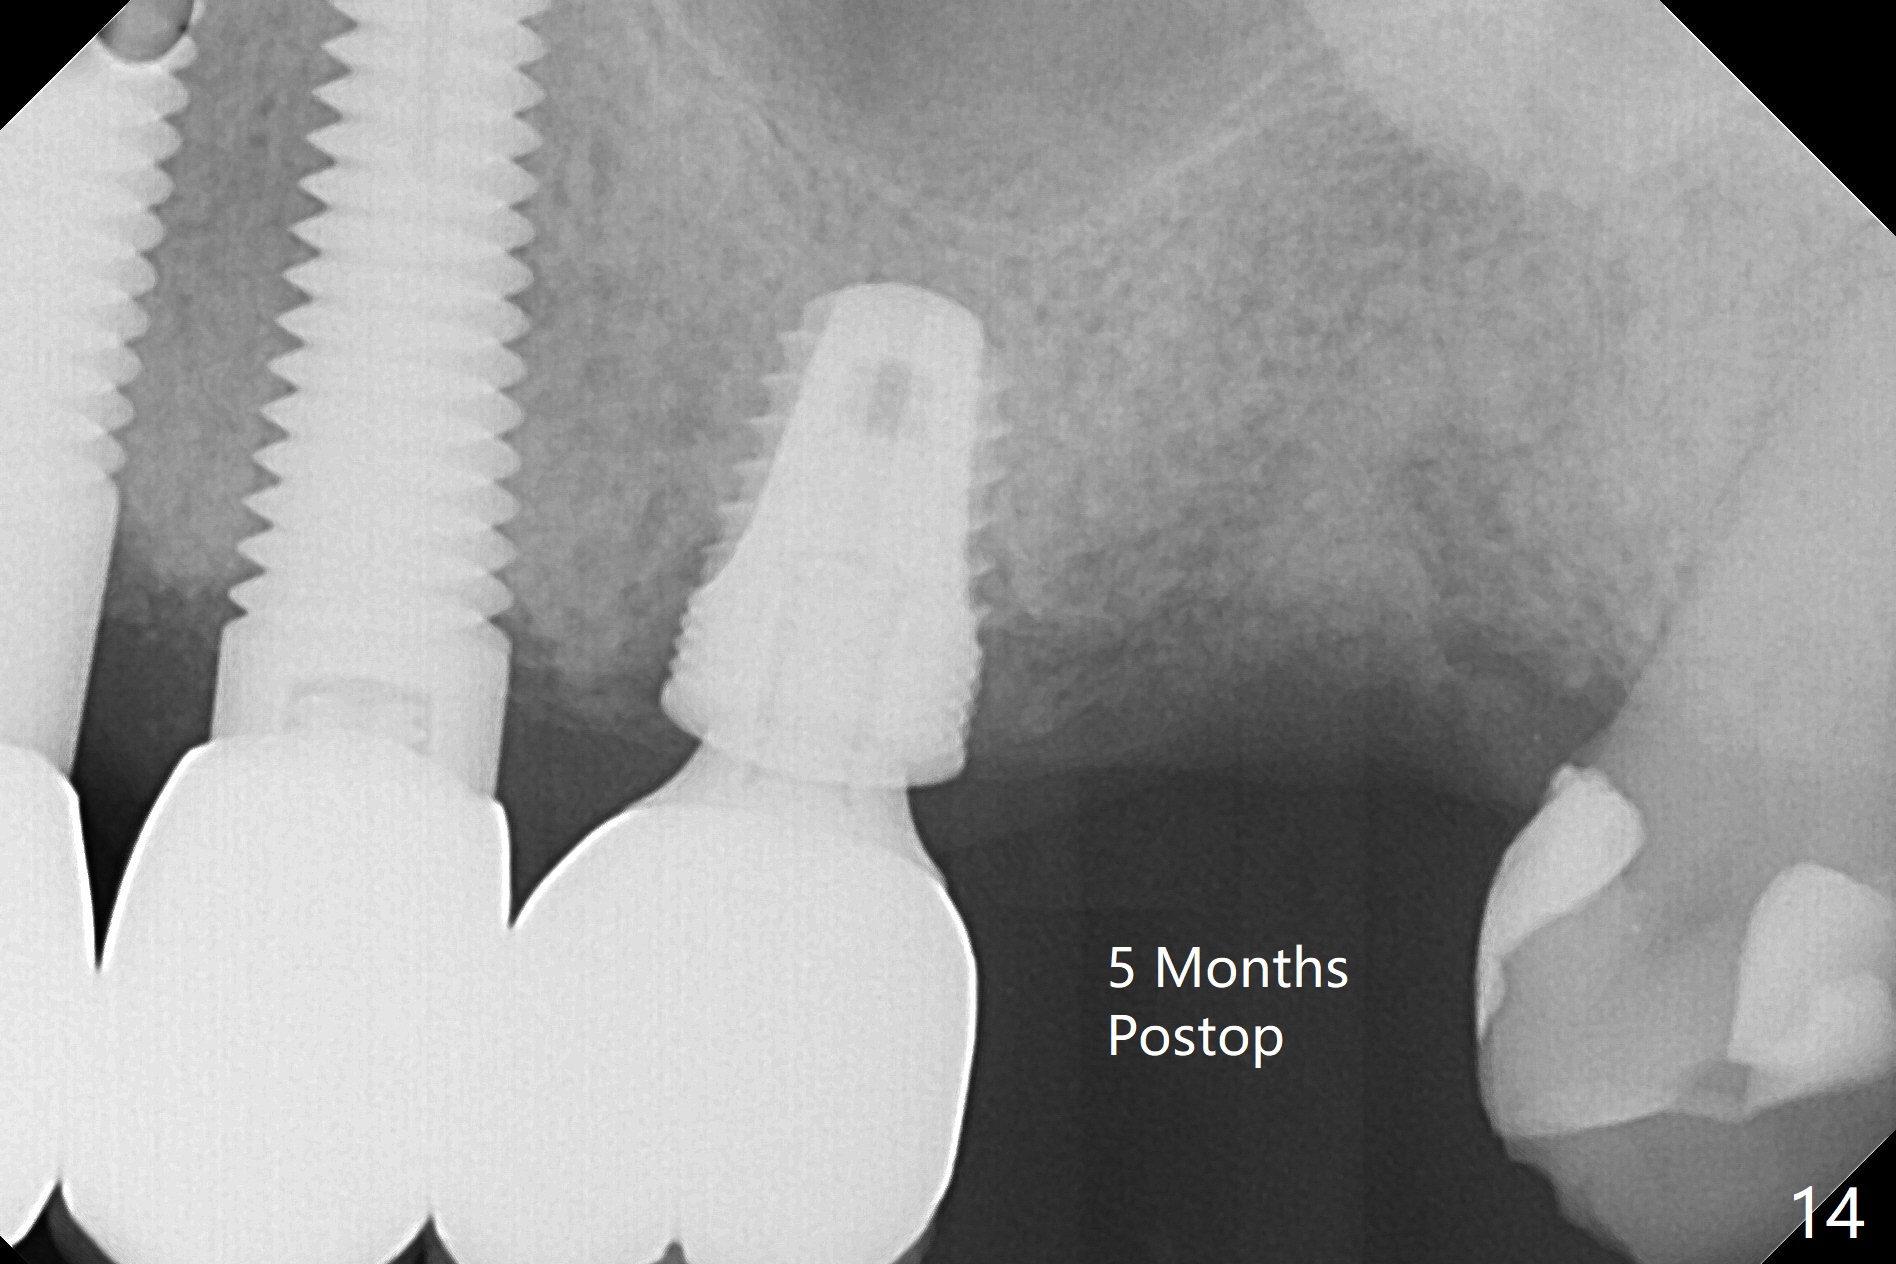

The 7x14 mm implant at #15 of a 89-year-old man is found to be loose ~ 1 year post cementation (Fig.1). After implant removal and debridement, bone graft is placed (Fig.2 G); the mesiocervical caries of the 3rd molar is removed, but not filled (*). With collagen membrane fixed with Chromic gut suture (Fig.3), setting acrylic is applied in the edentulous area, including the mesiocervical cavitation of the 3rd molar (Fig.4) for further retention. Bone graft gets lost following socket preservation at #31 with periodontal dressing. When the bone graft matures, a new implant (Fig.6 green) will get primary stability from the native bone, i.e., coronal to the sinus floor (Fig.5 F). The acrylic dressing (Fig.7 A) with a portion locking to the undercut of the neighboring crown (*) remains in place 5 weeks postop. When the dressing is cut off, the bone graft is exposed with odor (Fig.8,9 *). Periodontal dressing is applied. The distolingual portion of it gets lost due to brushing a day later. When he returns, the dressing is removed (Fig.10). It appears that the growing in gingival margin is pushing the bone graft out. A moment later after just a few rounds of swallowing, more graft is lost (Fig.11). We would love to leave the wound open, but the senior citizen complains of air leaking and requests reapplication of periodontal dressing. The bone graft is almost gone when the 2nd periodontal dressing is removed nearly 2 months postop (Fig.12). The tooth sensitivity disappears when MO caries is taken care of. The socket has a dimple 5 months postop (Fig.13), although it is filled with bone graft (Fig.14). Due to low bone density (~500 HU), sinus lift is required for implant stability with PRF (Fig.15). In fact the lab chooses not to do sinus lift.